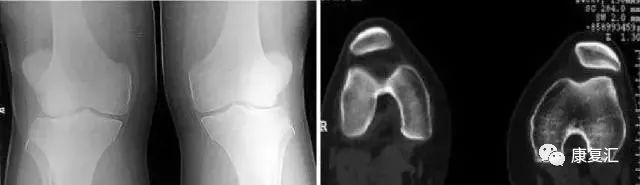

分裂 (二分)髌骨

常见于儿童,多双侧性。一般认为是正常骨化的变异,可在十几岁时融合。

症状:运动时疼痛或运动后疼痛,膝关节屈曲时疼痛、下跪时疼痛,上下楼梯时疼痛,行走时疼痛,受冷时疼痛。

分裂部扣击痛:可诱发有症状的分裂髌骨的疼痛,无症状者阴性。分裂骨片局部骨性隆起。 股四头肌萎缩, 髌骨摩擦音,大多无关节积液、跛行和关节活动度受限。有时需与骨折鉴别。